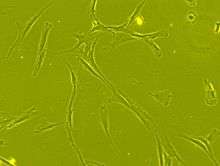

Cell transplantation is an important avenue for SCI research: the goal is to replace lost spinal cord cells, allow reconnection in broken neural circuits by regrowing axons, and to create an environment in the tissues that is favorable to growth.[52] A key avenue of SCI research is research on stem cells, which can differentiate into other types of cells—including those lost after SCI.[52] Types of cells being researched for use in SCI include embryonic stem cells, neural stem cells, mesenchymal stem cells, olfactory ensheathing cells, Schwann cells, activated macrophages, and induced pluripotent stem cells.[146] Hundreds of stem cell studies have been done in humans, with promising but inconclusive results.[135] An ongoing Phase 2 trial in 2016 presented data[147] showing that after 90 days, 2 out of 4 subjects had already improved two motor levels and had thus already achieved its endpoint of 2/5 patients improving two levels within 6–12 months. Six-month data is expected in January 2017.[148]